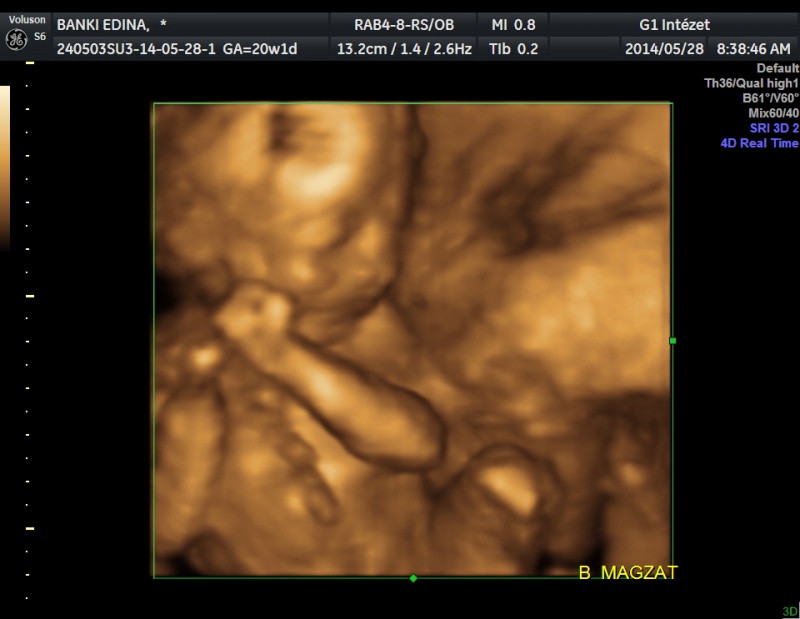

Kislánykáim vannak, a 4D-n egyértelműen látszott és mutogatták is magukat! ![]()

A méretek nagyon szórnak már, mensi szerint csak 20. betöltött hét van, ehhez képest az egyik baba kb. ezeket, de inkább a 21. heti adatokat produkálja: BPD 48, OFD: 60, AC: 165, FL: 33, a másik baba pedig egy héttel vagy többel nagyobb: BPD 54, OFD 64, AC: 166, FL:37

A kisebb baba becsült súlya 379 gr, a nagyobbiké 452 gramm. ![]() Nőnek mint a gomba.

Kiválasztottam két képet és egy mai pocakfotó: